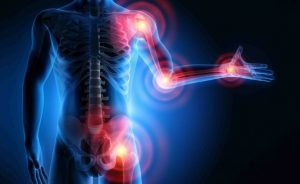

Artriti reumatoid është një sëmundje kronike autoimune e cila përveçse prek kyçet, mund të prekë…